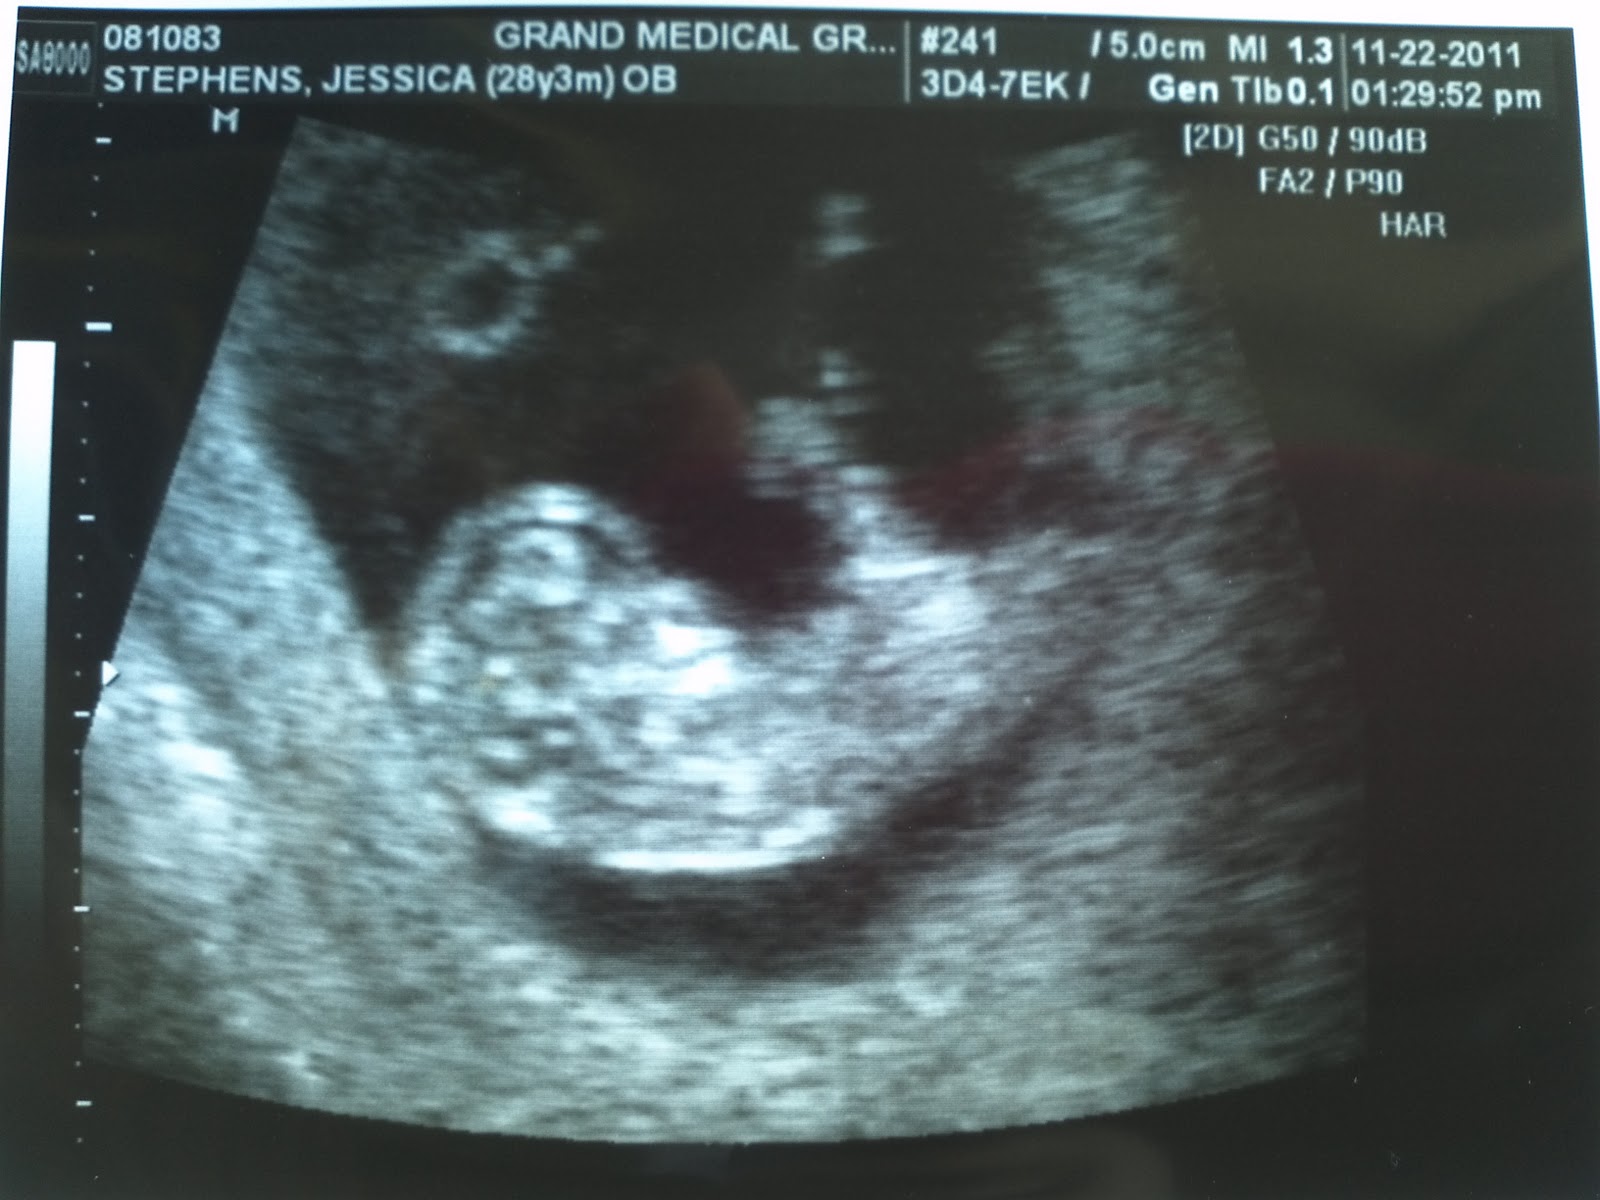

Dating Scan 11 Weeks 3 Days

If 12 week scan done pre 11 weeks will it need to be redone? (18 Posts) Add message | Report. hullabaloo Thu Nov Hello all! I am pregnant again immediately following a MC on 21st September so going by that date I am 9+3 but I have longer cycles anyway so believe more likely 8+3 but possibly less given the MC. My . Aug 29,  · I had my dating scan today, and I told them my 1st day of LMP (13/6/07) and said I was 11 weeks exactly. the scan said I was 9 weeks and 5 days and be. How accurate are dating scans? A dating scan is the best way to predict your due date (PHE ). The point of the scan is to work out how many weeks pregnant you are. You may have calculated the length of your pregnancy from the first day of your last menstrual period (LMP). However, conception doesn't actually occur until around 14 days after . If I can give you my 92 yr old grandmothers wise words. Please click here if you are not redirected within a few seconds. Although you can't feel it yet, your baby is doing a whole lot of wriggling and is now able to dating scan 11 weeks 3 days and somersault inside your womb! Get the 1 app for tracking pregnancy day by day - plus advice, guidance and valuable tools. I have literally seen my doctor then had the scan, so waiting for all these appointments to come through. Antenatal care for uncomplicated pregnancies.